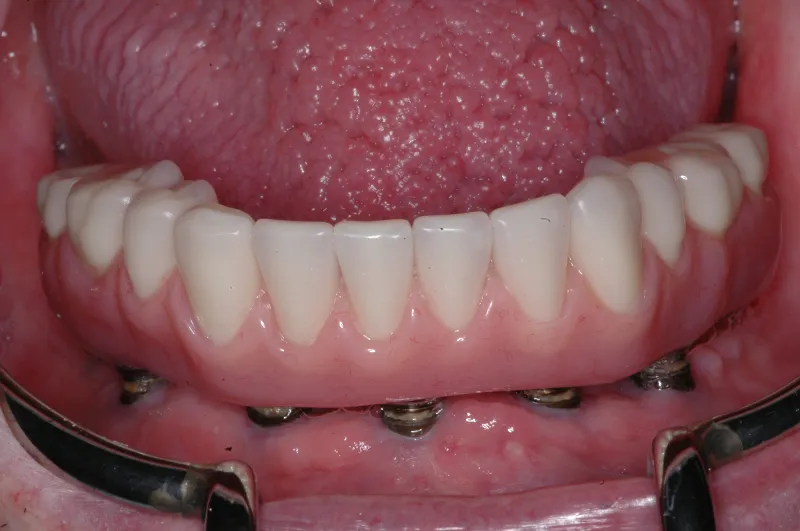

Implant dentures are designed to be fixed (screwed in place) or removable. The design is based on the number of implants present and the amount of bone loss that has already occurred. The fixed denture requires 4-6 implants . A removable implant supported denture can be made on as few as two implants. Sometimes the budget or insurance coverage will dictate which option you decide on. Most patients prefer the fixed type implant denture. These types of dentures eliminate the need for denture adhesive.